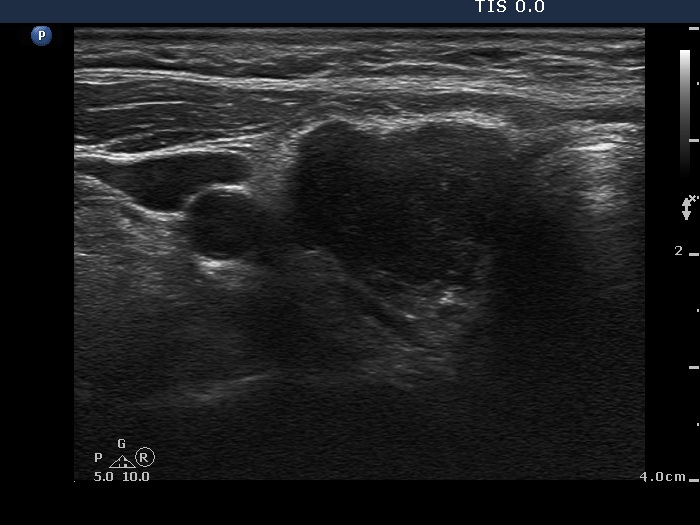

Ultrasonography: The right lobe was hypoechogenic, the left was moderately hypoechogenic. Both lobes were irregular in shape and were composed of several circumscribed areas surrounded with echonormal rim. The vascularization was significantly increased.

The sonographic pattern is specific. At first sight both lobes, particularly the right one seems to be nodular. First, the lobes are composed of a central hypoechogenic part surrounded with an echonormal rim, therefore it seems like the lobes were composed of a large hypoechogenic nodule. Second, connective tissue, perhaps a scar makes an impression in the ventral and in the dorsal part of the right and the left lobe, respectively. This makes an appearance as the lobes were composed of two nodules or one lesion with irregular lobulated and spiculated margins. In fact, the scar is responsible for the irregularities seen on the surface of the hypoechogenic mass, and regarding the hypoechogenic mass, the inclinations are the primary cause.